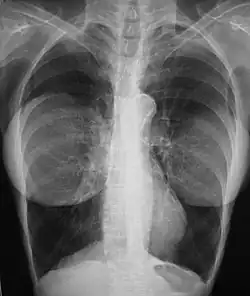

Breast Implant: the chest X-ray of a woman with bilaterally emplaced breast implants shows that the prostheses are radiographically opaque, and are foreign objects in her body, but not of her body.

In the study Long-term Health Status of Danish Women with Silicone Breast Implants (2004), the national healthcare system of Denmark reported that women with implants did not risk a greater incidence and diagnosis of autoimmune disease, when compared to same-age women in the general population; that the incidence of musculoskeletal disease was lower among women with breast implants than among women who had undergone other types of cosmetic surgery; and that they had a lower incidence rate than like women in the general population.[97][98]